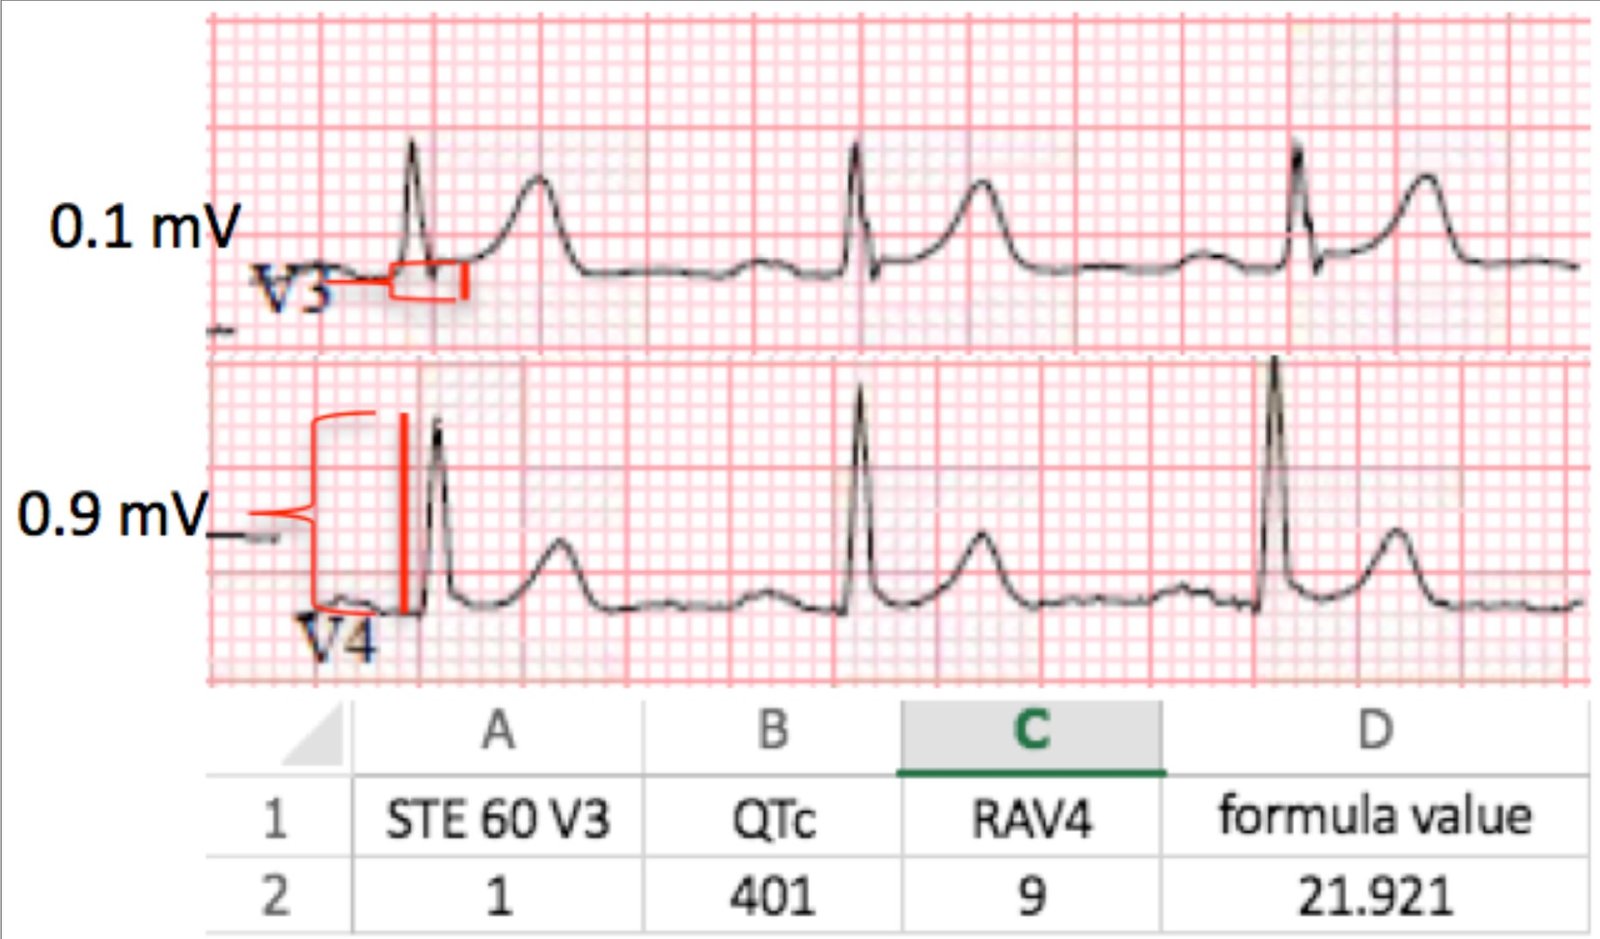

Initial ECG with measurements and calculation

Magnified view of measurements and calculation

A “formula value” greater than 23.4 is both sensitive and specific for acute LAD occlusion. Therefore, this ECG would not have met the criteria for ACO by this formula.

The 4-variable formula score (using QRS amplitude in V2 = 9mm) is 16.59, which is below the formula’s cutoff value of 18.2 (also more indicative of benign variant than OMI).